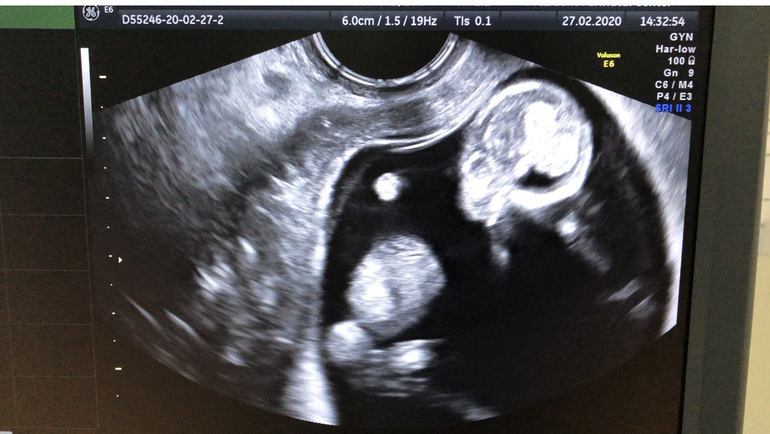

Первый скрининг пройден ☀️🐣👏

Результаты: УЗИ, КТГ, доплера, скринингаВсе у малыша хорошо 🙏🏻

Срок по узи 12,4

Ктр 60

Твп 1,1

Чсс 155

Пол предположили мальчик - сказали торчит что то 😀 но у девочек тотточно так же торчит) вообщем вот что значит скрининг по ОМС)

Можем кто на фото разглядит 🤪